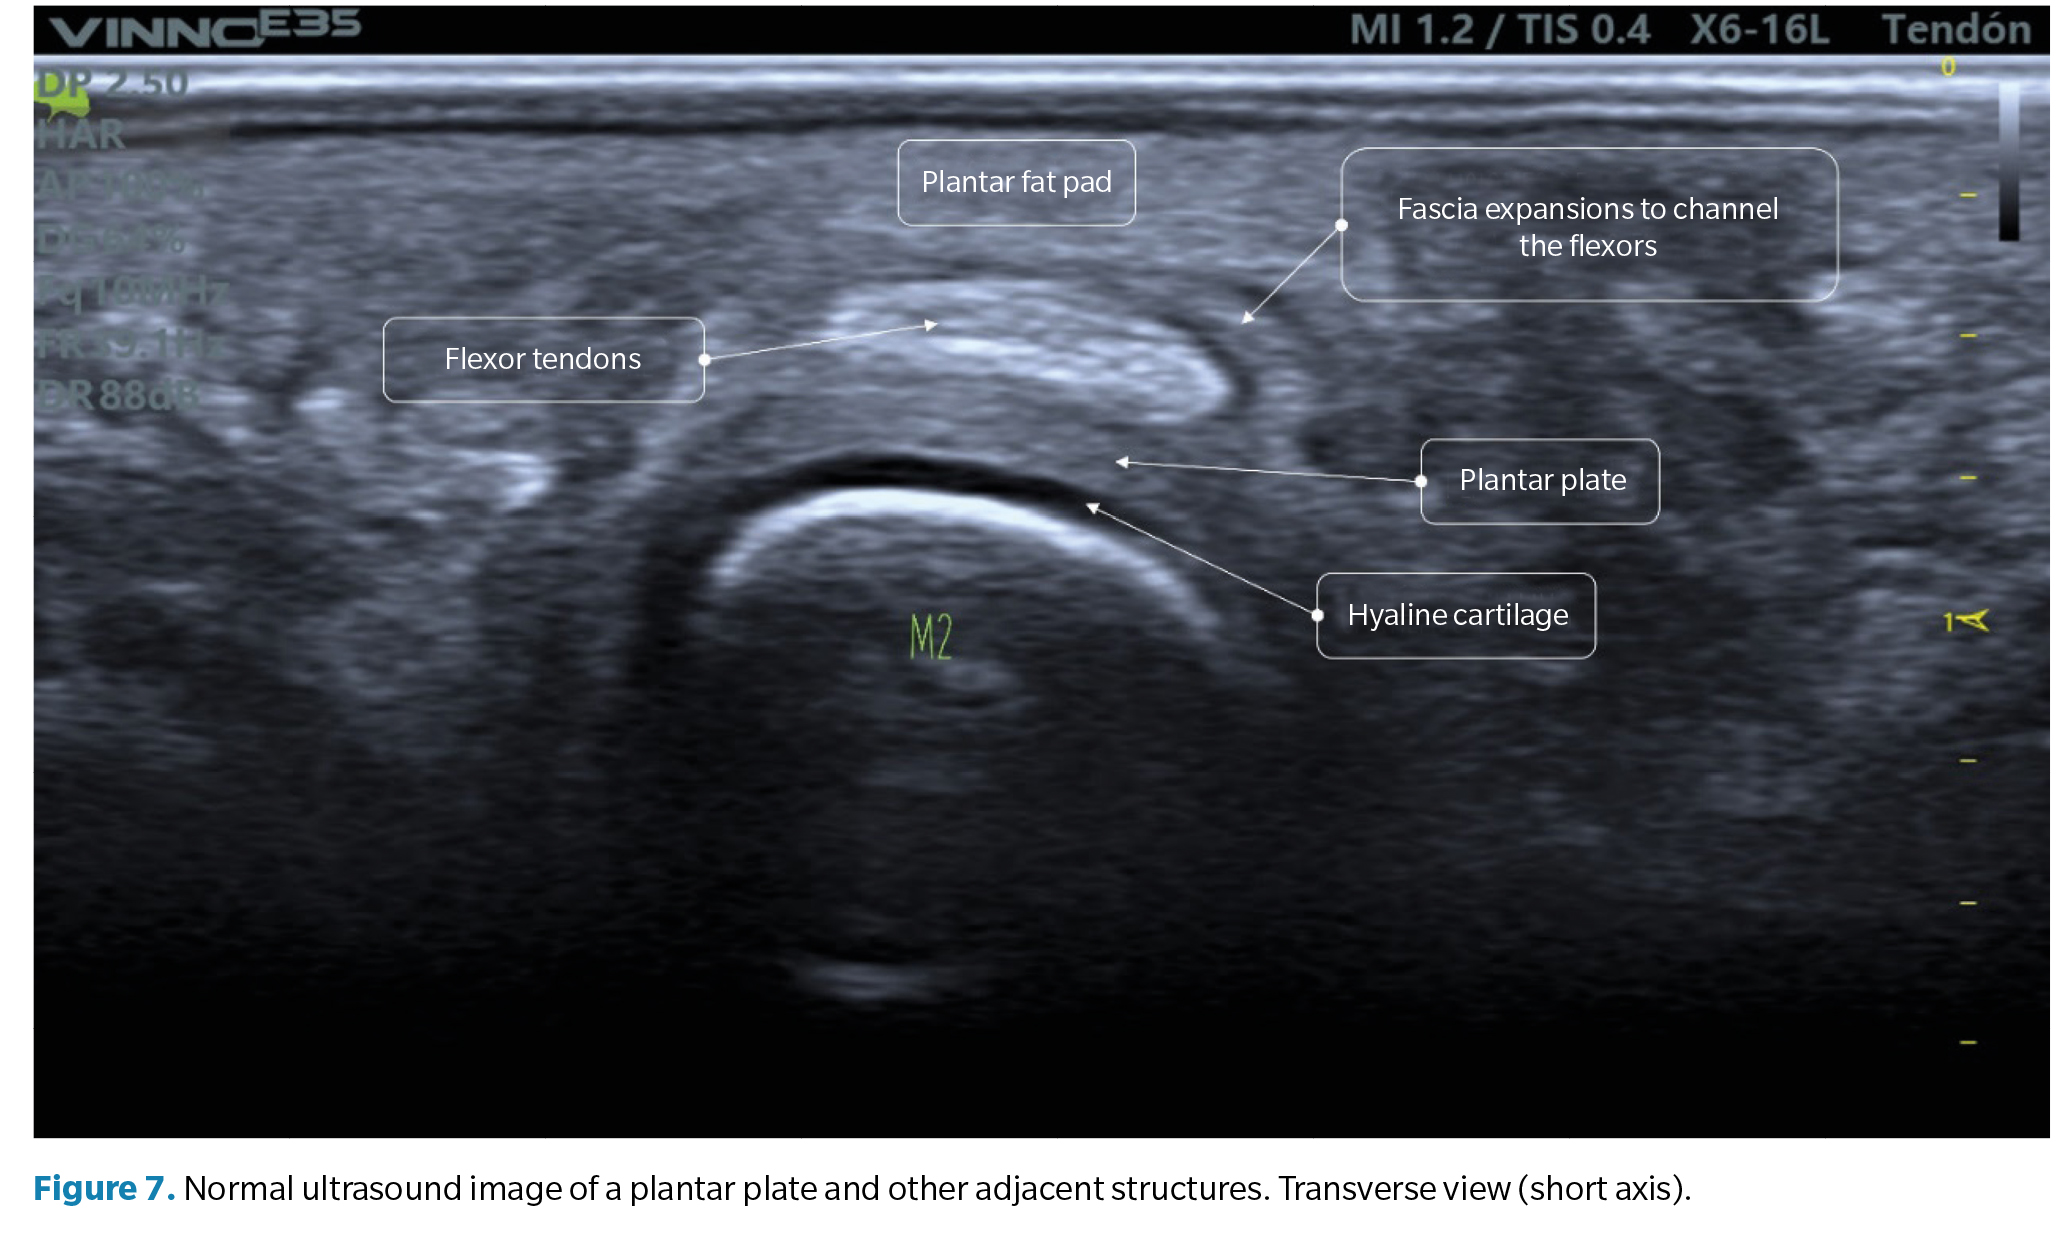

• Transverse view (short axis): the plantar plate will have a curved shape that cradles the metatarsal head. The echotexture is equally granular, although in this exam, the mottled appearance may be more heterogeneous, reflecting the longitudinal arrangement of collagen bundles. The flexor tendons can be seen over the plate and can be easily identified using anisotropy maneuvers (Figure 7).